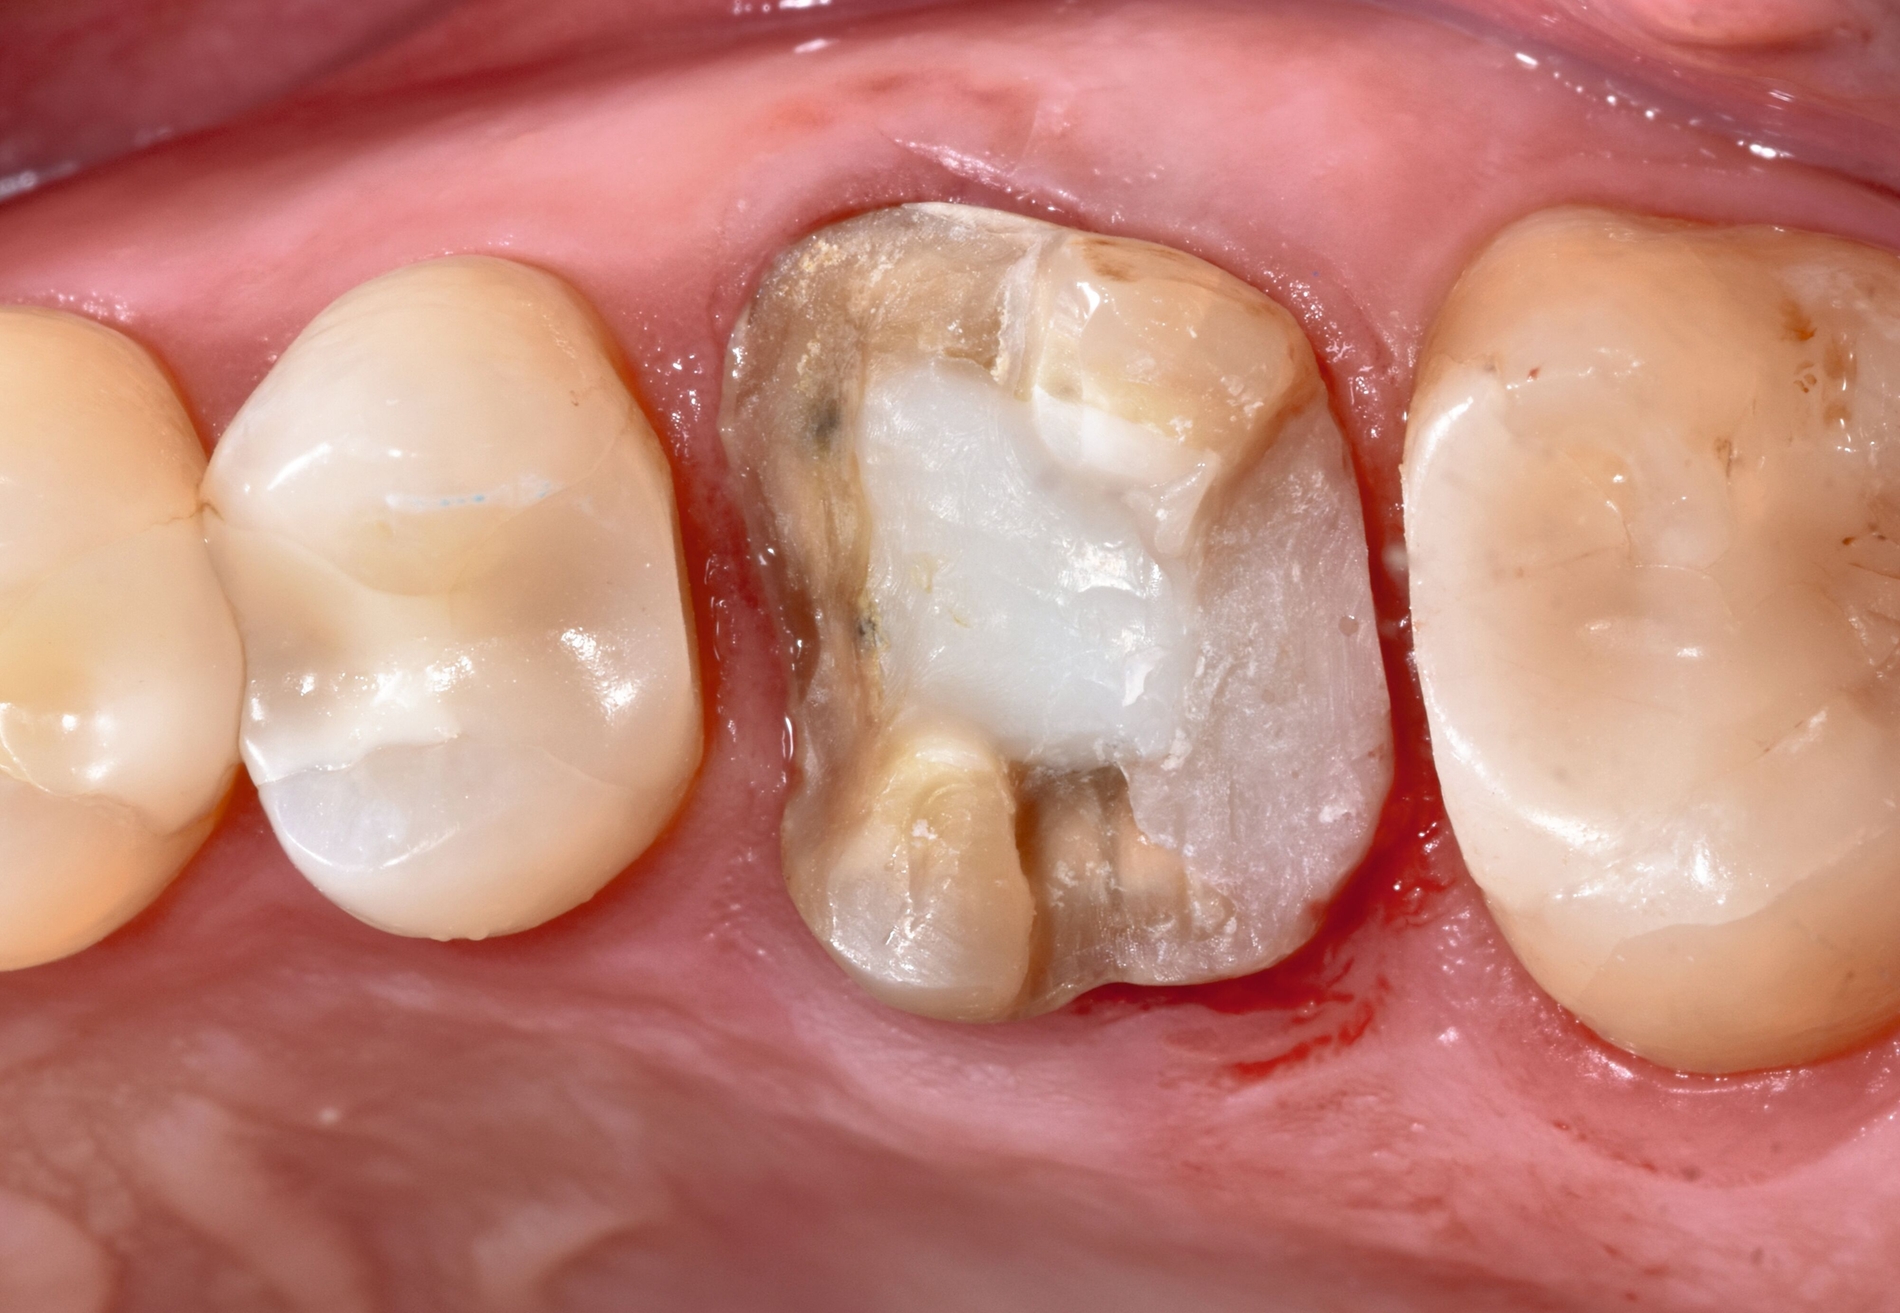

Zahn 26 ist vor etwa 20 Jahren endodontisch behandelt und anschließend postendontisch mit einer indirekten keramischen Restauration versorgt worden. Bei der klinischen und der röntgenologischen Diagnostik fällt distal an Zahn 26 eine bis in den subgingivalen Bereich reichende Sekundärkaries auf. Die Wurzelkanalfüllung erscheint homogen und randständig, es besteht kein Hinweis auf eine periapikale Osteolyse. Weiterhin besteht kein Anhalt auf eine parodontale Erkrankung. Bis zur definitiven restaurativen Therapie wird das freiliegende Dentin mit einer Schicht Flow-Komposit abgedeckt (Abbildung 1).

Zu Beginn werden die frakturierte Teilkrone und das provisorisch aufgebrachte Flow-Komposit entfernt, der kariöse Defekt dargestellt und die Wurzelkaries exkaviert. Mit einem speziellen 10-Methacryloyloxidecyl-Dihydrogenphosphat(MDP)-haltigen Cleaner wird das mit Speichel kontaminierte Wurzeldentin gereinigt und für die Adhäsivtechnik vorbereitet (siehe Materialliste). Im hier gezeigten Fall kann trotz des subgingivalen Defekts zirkulär eine spezielle Ringbandmatrize angelegt werden, die zusätzlich mit einem Keil abgedichtet wird.

Der Effekt durch die Vermischung der beiden Kompositmaterialien in ungehärtetem Zustand besteht in der Optimierung der marginalen Adaptation und der Verbesserung der Randqualität am subgingivalen Bereich. Nach Abnahme der Matrize erfolgt eine erneute Lichtpolymerisation und die Ausarbeitung der subgingivalen Restaurationsränder mithilfe eines sichelförmigen Skalpells (Nr. 12), von Finierdiamanten und gegebenenfalls von oszillierenden diamantierten Shape-Feilen (Abbildung 2).